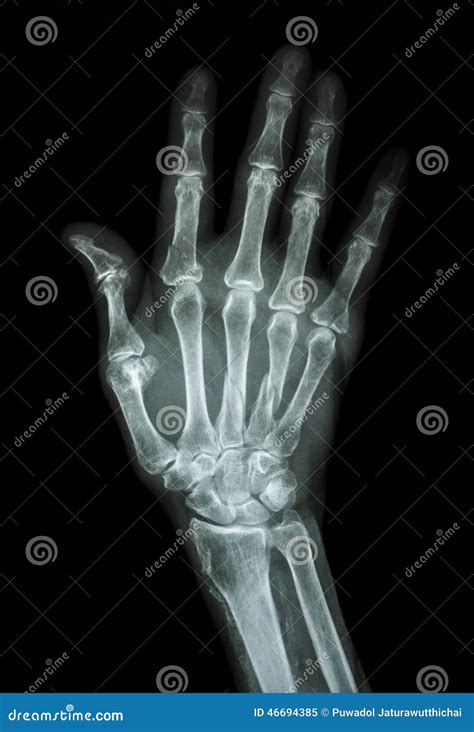

Diagnosing a Broken Index Finger

Diagnosing a broken index finger typically involves a physical examination and imaging tests. Your healthcare provider will:

• Examine the injured finger to assess the extent of the damage.

• Order X-rays to visualize the bone and determine the type and severity of the fracture.

• In some cases, additional imaging tests such as CT scans or MRIs may be required for a more detailed view.

Based on the findings, your healthcare provider will recommend the appropriate treatment plan.